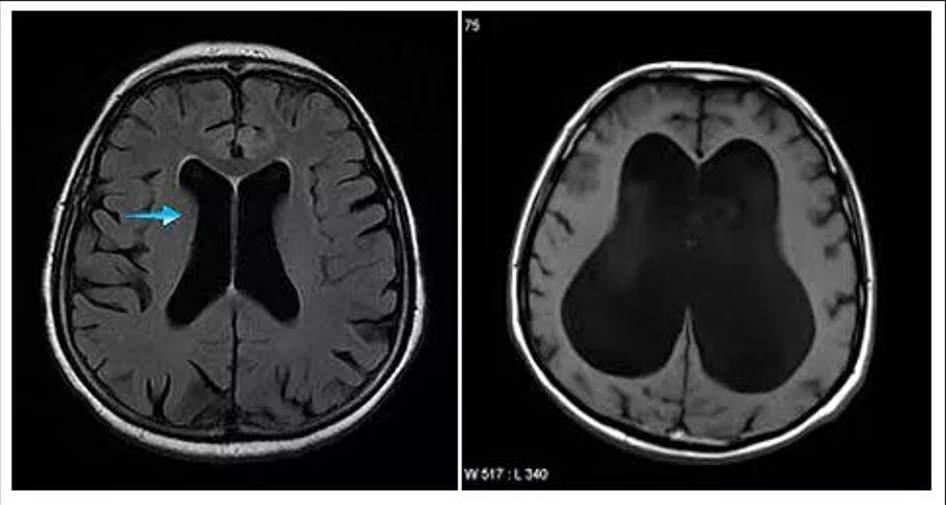

Hidrosefali, beyinde ve omurilikte üretilerek beyni dış tesirlerden müdafaaya yardımcı olan beyin omurilik sıvısının (BOS), beyindeki boşluklarda birikmesi ve baş içindeki basıncı artırması durumudur. Beyin omurilik sıvısı, bulunması gerekenden daha fazla olduğunda beyin dokularına ziyan verir, kafatasının fizikî yapısını bozar ve beyin işlevlerinde kalıcı bozulmalara neden olabilir.

Bebeklik devrinde kendisine “hidrosefali” teşhisi konulan adam, kafatasına stent takıldığını ve 14 yaşındayken geri çıkarıldığını belirtti. Doktorlar, adamın hastalığından ötürü beyninde sıvı biriktiğini ve bu nedenle 30 yılda beyninin yavaş yavaş tahrip olduğunu düşünüyorlar.